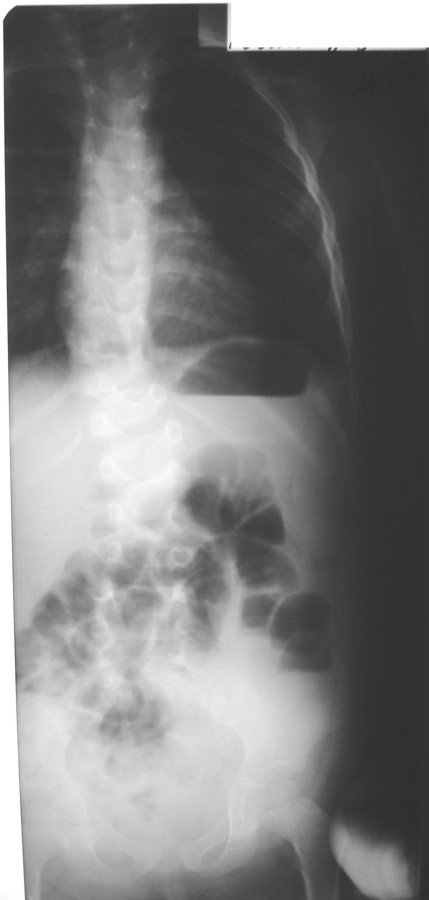

Уважаемые коллеги!Окажите, пожалуйста, консультативную помощь в данном случае.Мальчик,

2008 г.р. Жалобы родителей на деформацию позвоночника и мягких тканей, быструю

утомляемость.Анализ заболевания: деформацию позвоночника родители заметили, когда

ребенок стал ходить. Обратились в гор. больницу по месту жительства, где была произведена

рентгенография позвоночного столба.При осмотре: определяется перекос таза вправо, S

образное искривление позвоночника, ассиметрия надплечий, треугольников талии,

правосторонний мышечный валик в поясничном отделе позвоночника.На рентгенограммах с 1

грудного по 1 крестцовый (прямая проекция) аномалия развития позвоночника: левосторонний

клиновидный позвонок 3 грудного, правосторонний клиновидный позвонок 11 грудного.

Добавочный левосторонний клиновидный позвонок между 2 поясничным и 3 поясничным

S-образный с ротацией тел. Перекос таза вправо.Методы дообследования?Тактика

лечения?Заранее благодарим!